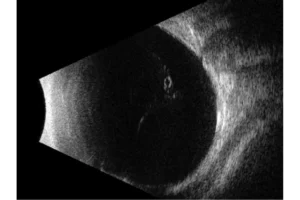

Quantel Medical heeft een sprong voorwaarts gemaakt met de nieuwe technologie met 5 ringen op een 20 MHz-sonde. Het principe is om om en om ultrasone geluidsgolven uit te zenden via 5 concentrische transducers in dezelfde sonde. Deze technologie:

- Verhoogt het focusgebied

- Vermindert de laterale resolutie van 250 naar 200 µm, oftewel met 25%

- Behoudt een hoge axiale resolutie

Het volledige oog is nu zichtbaar met een uitstekend detailniveau.

Verlengde scherptediepte van 70%

De ringtechnologie verdubbelt praktisch de scherptediepte. De 20 MHz-ringvormige sonde heeft een verlengde scherptediepte van 70%, waardoor het mogelijk is om pathologieën van het glasvocht, het netvlies en verder tegelijkertijd te observeren zonder concessies te doen aan de beeldresolutie.